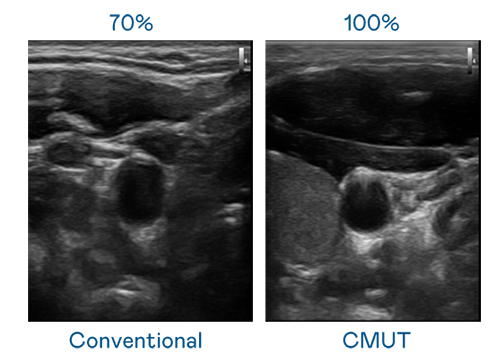

CMUT 技术是一种用电容式微机电元件来产生超音波讯号的技术。与传统 PZT 压电式技术相比,CMUT 频宽增加 30%,更宽频的超音波讯号让影像解析度大幅提升,是实现高影像品质医疗超音波扫描、促进精准医疗发展的关键技术。

大频宽带来超清晰影像

超音波影像的解析度高低,首先取决于探头能发出的讯号频宽。294俄罗斯专享会 CMUT 可提供高清晰的超音波讯号,提供高频宽、高灵敏度、影像纹理细节更高的超音波影像,协助医护人员缩短影像判读时间及利用精准的医疗影像进行诊断。